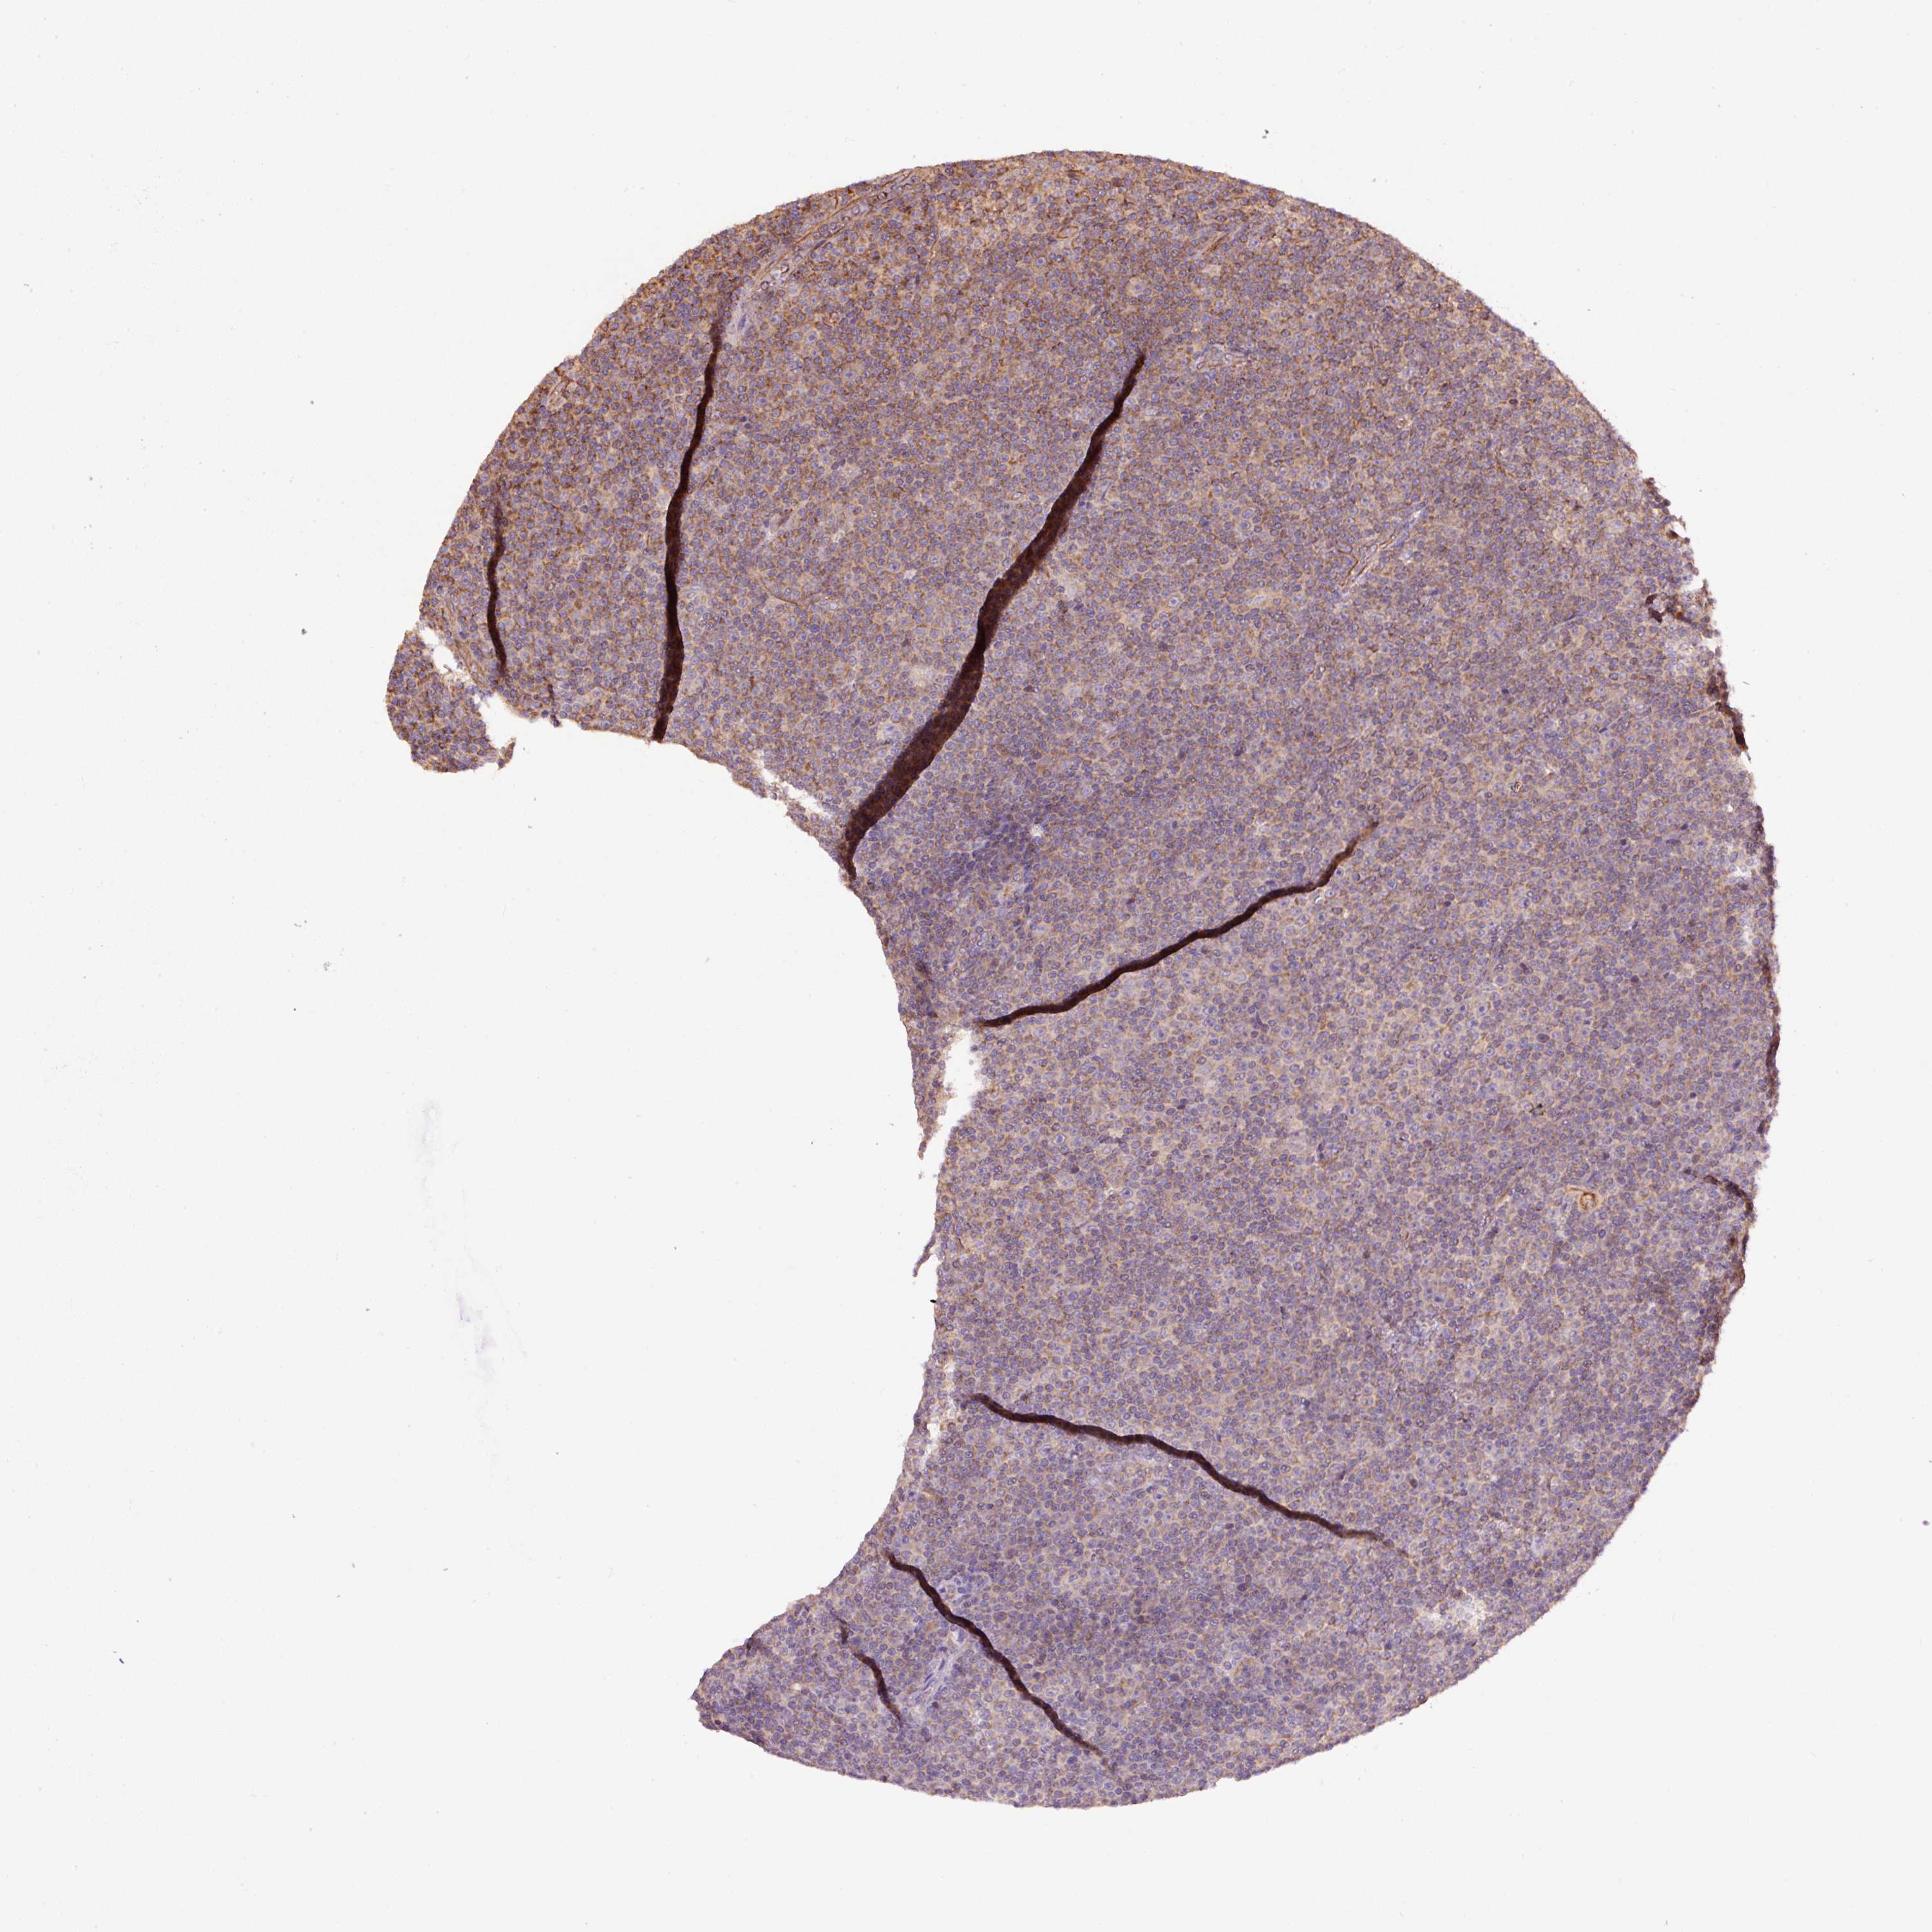

CANCER LYMPHOMA Show tissue menu

LYMPHOMA - Protein expressioni

A mouse-over function shows sample information and annotation data. Click on an image to view it in a full screen mode. Samples can be filtered based on level of antibody staining by selecting one or several of the following categories: high, medium, low and not detected. The assay and annotation is described here.

Each image is clickable and will lead to virtual microscopy that enables deeper exploration of all samples and also displays staining intensity scores, fraction scores and subcellular localization as well as patient and tissue information for each sample.

Antibody HPA051162

Antibody HPA053502

Antibody CAB018734

Staining

High

Medium

Low

Not detected

Intensity

Strong

Moderate

Weak

Negative

Quantity

>75%

75%-25%

<25%

None

Location

Nuclear

Cytoplasmic/membranous

Cytoplasmic/membranous,nuclear

Hodgkin's disease, NOS

Malignant lymphoma, non-Hodgkin's type, High grade

Malignant lymphoma, non-Hodgkin's type, Low grade